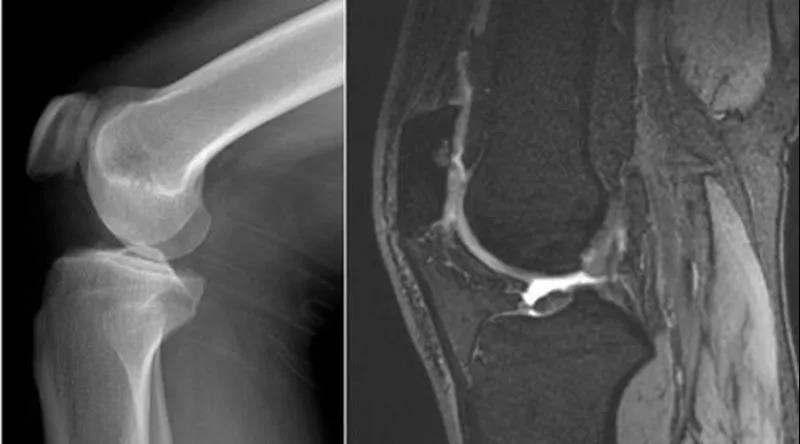

膝关节腔积液的原因:

1、受伤(与运动有关)膝关节扭伤、半月板损伤、侧副韧带或交叉韧带损伤。2、感染(结核)。3、类风湿性关节炎、滑膜炎。

当关节退变、运动过力或创伤,使得关节腔内乳酸、组胺、缓激肽、前列腺素和神经肽等被激活,能够引起疼痛,同时膝关节腔内出现大量关节腔积液,压力增加,膝关节肿胀。